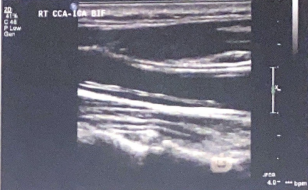

Patient presents with recent history of syncope. New onset of HTN and HX of smoking 1 pack per day (ppd) x 25 years.

Carotid ultrasound exam ordered. Considering following questions and please answer.

1. In patient presentation, which item is the symptom for carotid ultrasound exam?

2. In patient presentation, identify the risk factors for atherosclerosis and carotid artery disease.

3. Consider image, which vessel contain some blue colors?

4. Is the 'blue' pathological?

5. What is the color blue representing?

Syncope

HTN and smoking

Prox ICA (bulb)

no

eddie currents from flow reversal in bulb